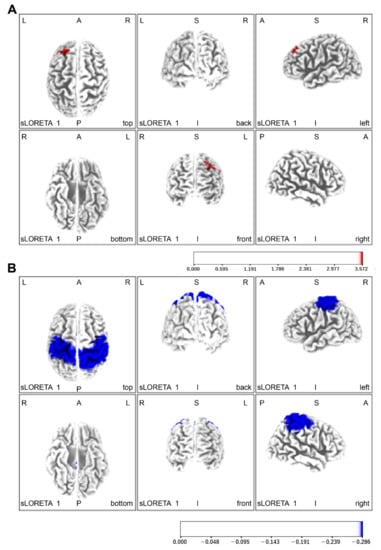

| Task Conditions | Brodmann Area | Neural Activity Values | |||||

|---|---|---|---|---|---|---|---|

| x | y | z | Brain lobe | (μA/mm2) | |||

| Peg manipulation practice (left hand) | |||||||

| Without Yubi-Recorder (red) vs. With Yubi-Recorder (blue) | |||||||

| Red | −25 | 40 | 45 | Left anterior cephalic lobe | Anterior cephalic eye field | 8 | 0.13 |

| Blue | −30 | −85 | 40 | Left posterior cephalic lobe | Visual field | 19 | 6.75 |

| Pre-intervention (red) < Post-intervention (blue) | |||||||

| blue | −40 | −55 | 60 | Left parietal lobe | supramarginal gyrus | 40 | 6.76 |